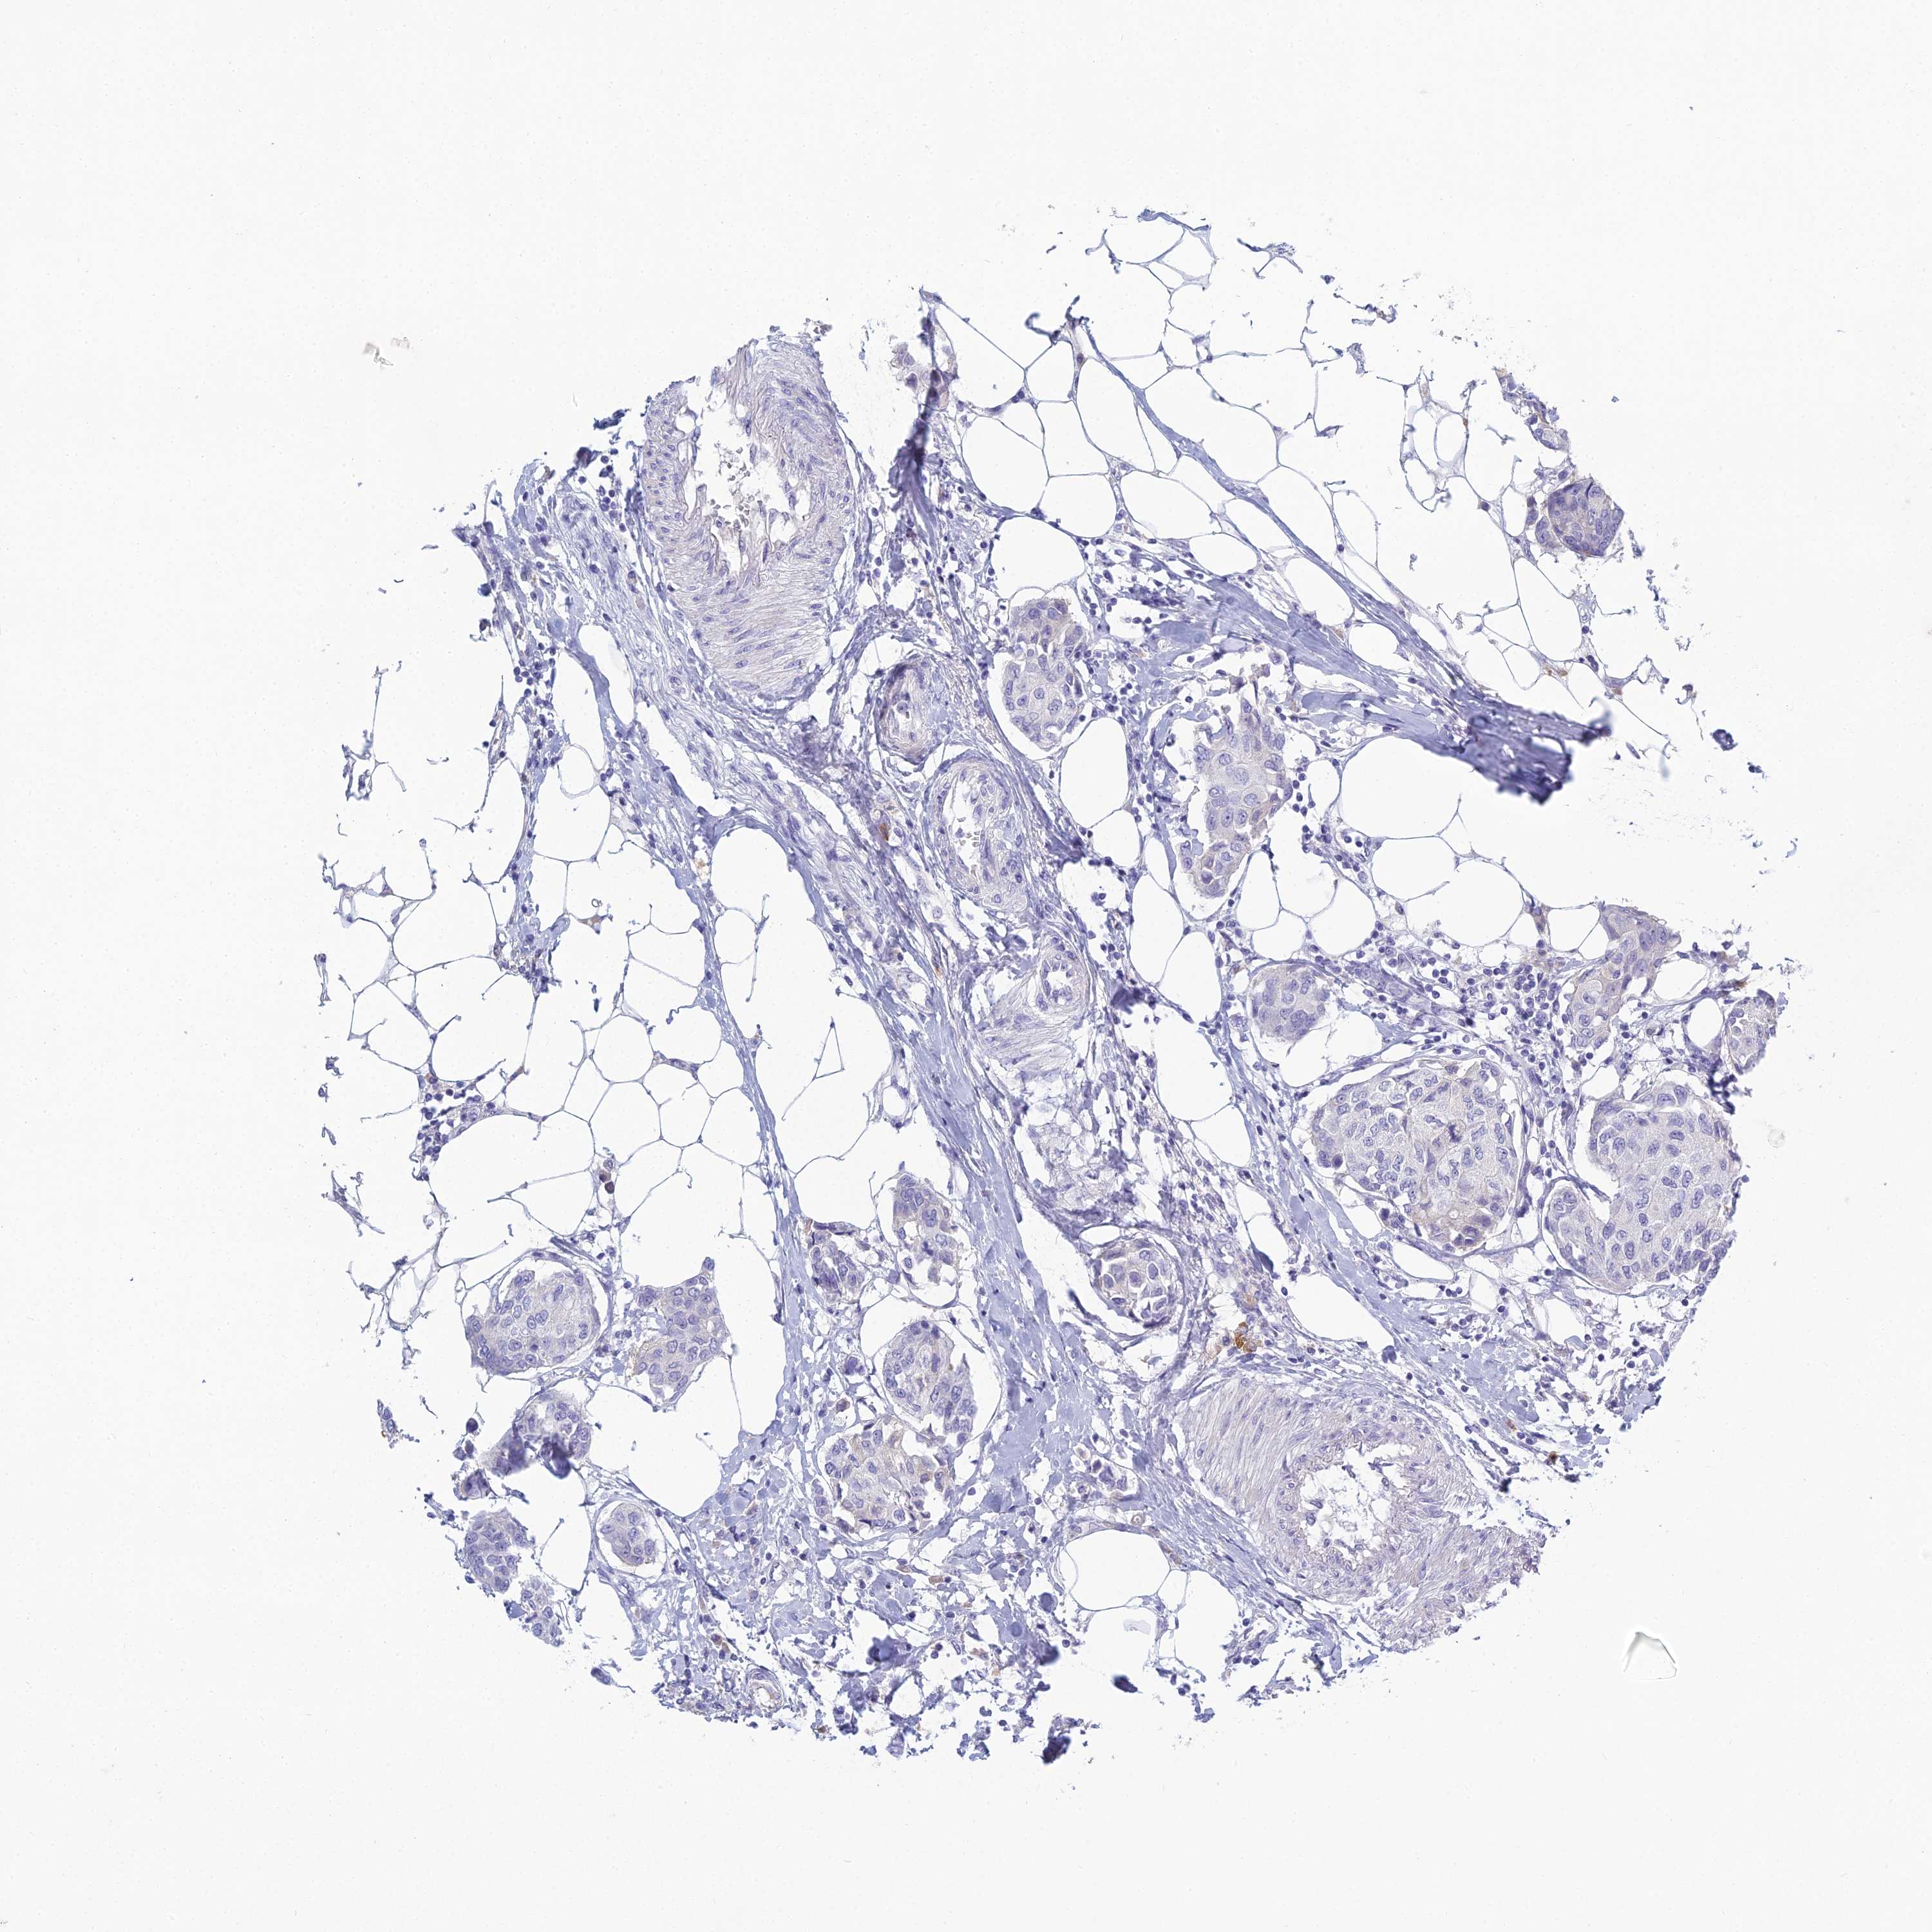

BRCA TCGA BRCA VALIDATION PROTEIN EXPRESSION

ANTIBODIES

AND

VALIDATION